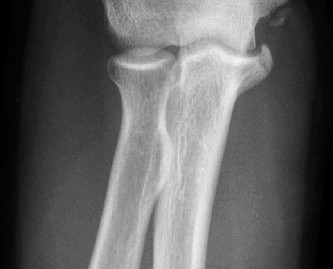

Standard radiographic evaluation of the thrower's elbow must include true anteroposterior (AP), lateral, oblique, and axial (cubital tunnel) views. In this patient, the AP view may appear relatively unremarkable, though subtle hypertrophy of the medial epicondyle or radiocapitellar sclerosis may be noted. The true lateral radiograph is highly informative, often demonstrating the presence of a posterior olecranon osteophyte.

However, the most critical view for diagnosing VEO is the internal rotation oblique view, or a specialized axial view of the olecranon fossa. In our patient's radiographs, we observe a distinct, hypertrophic osteophyte on the posteromedial aspect of the olecranon process. There are also faint radiopacities within the posterior compartment, highly suggestive of intra-articular loose bodies resulting from the fragmentation of these osteophytes.